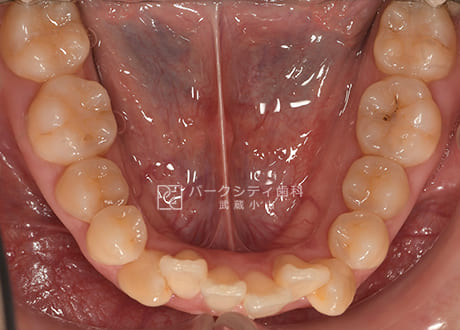

下顎術前

下顎術後